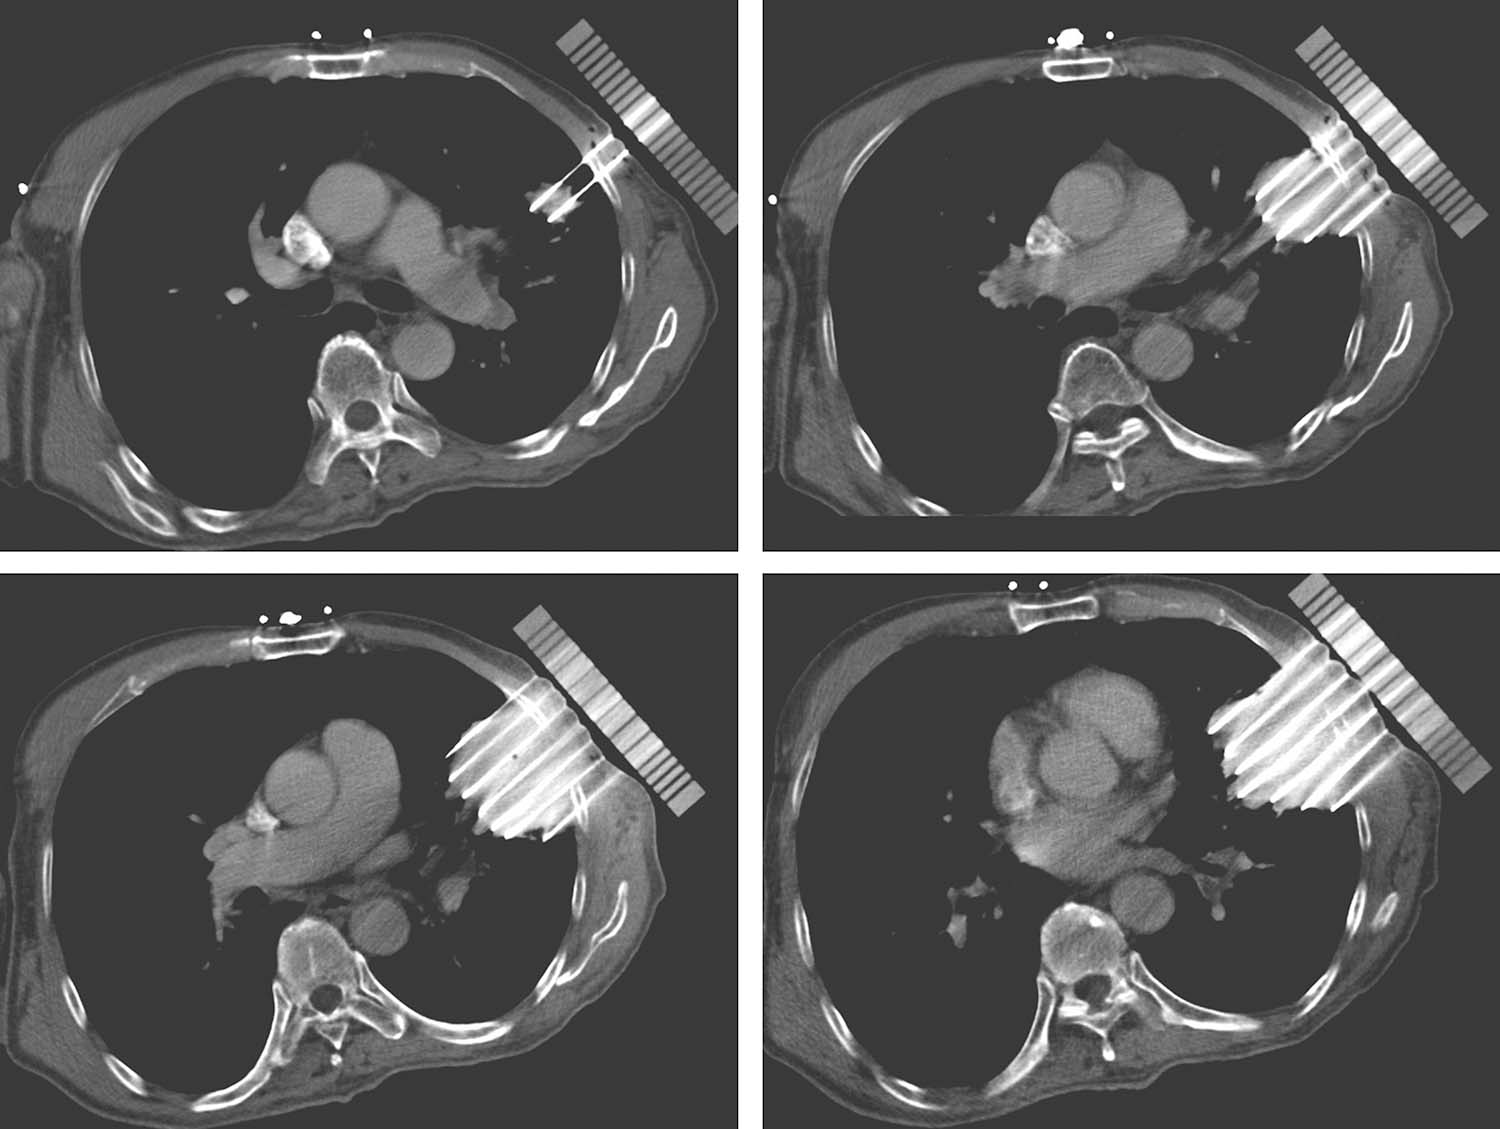

术前手术体位真空垫固定患者,行CT扫描,勾画靶区及危及器官,三维重建,查看靶区与危及器官的解剖关系(图4-4-6)。根据医师给定的处方剂量及粒子活度设计进针路径及粒子分布,计算等剂量分布,得出术前DVH图。计划审核无误后将数据传送至3D打印机打印模板。

术中根据术前计划体位摆放患者手术体位,采用负压真空垫固定,消毒铺巾后再次激光线定位患者。患者位置无误后将模板放置于患者体表,激光线校准模板位置。然后在预设的定位针道内穿刺定位针,激光线校准位置。定位针穿刺到位后扫描CT,观察定位针实际位置与术前计划一致后穿刺其他植入针,所有植入针到位后扫描CT,确认植入针实际针道与术前计划是否一致,如果不一致,可在相应辅助孔重新穿刺。所有针道位置无误后按照术前计划植入粒子。粒子植入完毕后扫描CT,比较实际粒子位置与计划位置是否一致,如有剂量不足区域及时补植。(图4-4-7)

图4-4-6 三维重建查看靶区与危及器官的解剖关系

图4-4-7 模板位置无误后在模板引导下一次性穿刺所有穿刺针